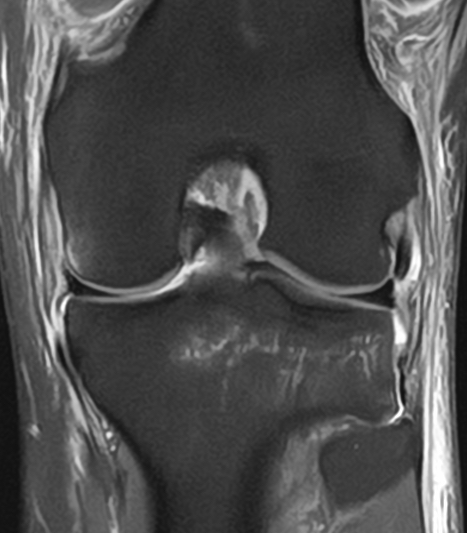

Polven magneettikuva edestä

Etu-taka-suuntainen (koronaali) kuva.